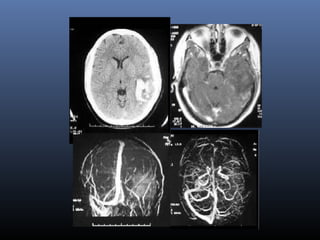

 One of top ten causes of childhood death

Neonatal hypoxia - findings

Central- Basal ganglia, Ventrolateral thalami, Brainstem

Peripheral-Peripheral cortex, adjacent whitematter

Peripheral Focal

FLAIR may not detect acute lesions

DWI, ADC values may be normal intially

Initial DWI , may not correspond to the final infarct volume

DELAYED CELL DEATH MECHANISMS